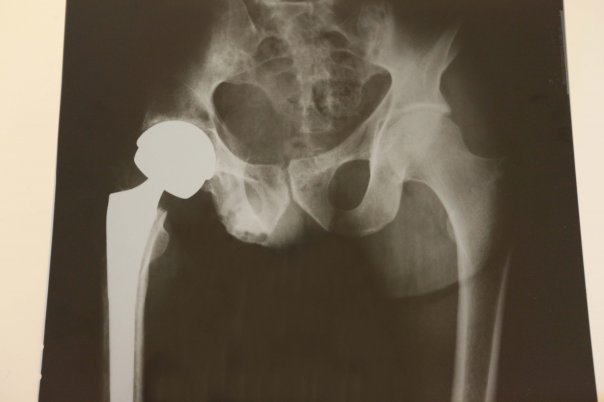

I wanted to share a pic of my cervelo p3 carbon bike wreck carbon failure where a car hit me... but suffice to say it was Soooooo bad I erased all the pics except for the before-

and a radiographical "after":